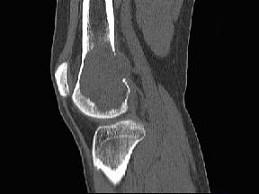

问题 患者,女,38岁,因右大腿远端部有疼痛,可摸到肿块,请结合所提供图像,选择最佳选项 ( )

选项 A、动脉瘤样骨囊肿 B、骨巨细胞瘤 C、骨囊肿 D、纤维异常增殖症 E、非骨化性纤维瘤

答案 B